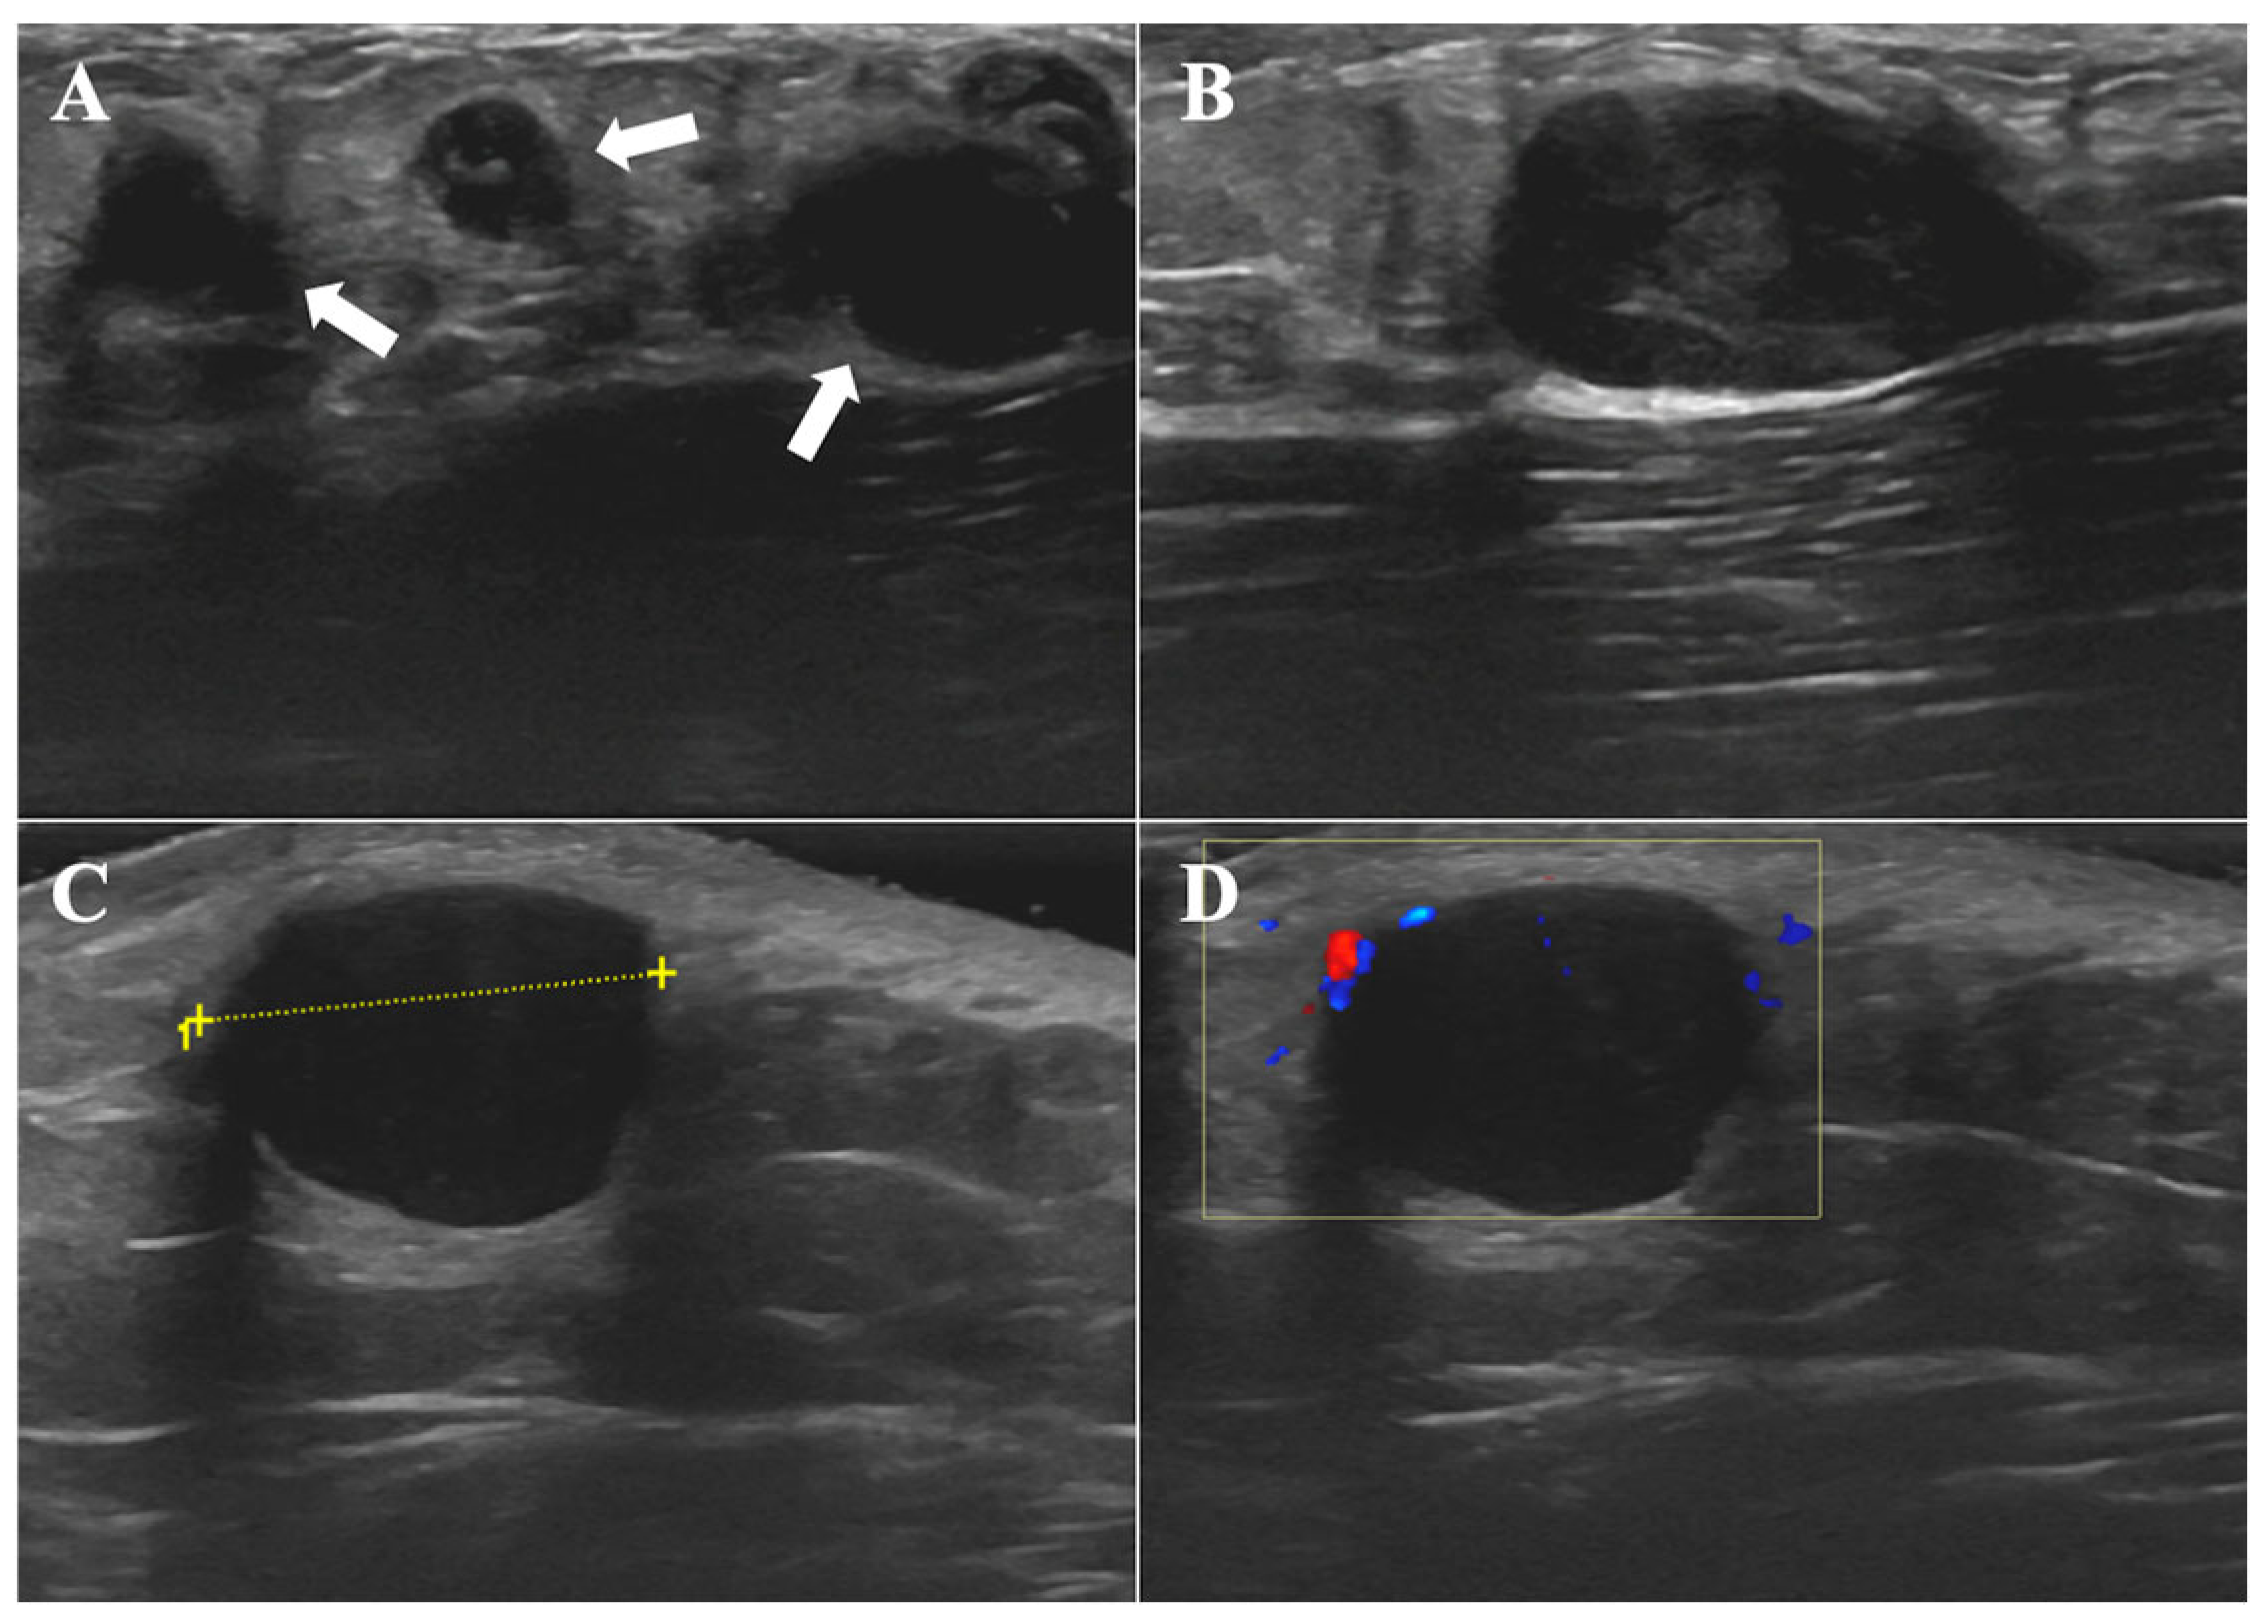

2.3.2. Imaging Studies

| Physical examination | an irregular, dark red plaque with multiple firm, smooth-surfaced nodules | a dark red, firm, freely mobile nodule with a smooth surface | several mobile, firm, subcutaneous nodules with smooth surfaces |

| HFUS features at presentation | |||

| Regular shape | − | + | + |

| Well-defined borders | − | − | + |

| Echogenicity | hypoechoic | hypoechoic | hypoechoic |

| Involvement layers | epidermis, dermis and subcutaneous tissue | dermis | subcutis |

| CDFI features at presentation | |||

| Abundant vascularity | + | − | − |